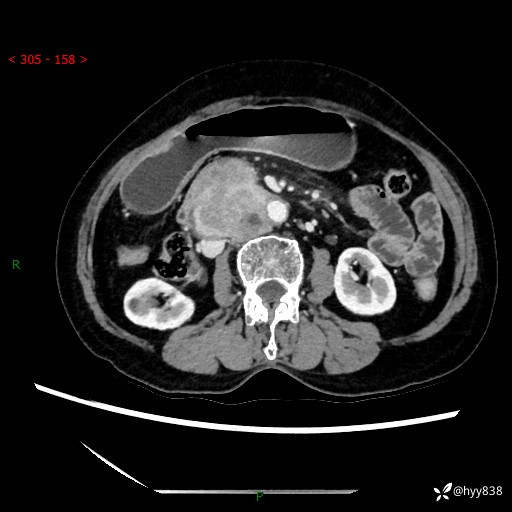

71岁/女,腹痛1月余。腹膜后肿物,间质瘤 VS 副节瘤 VS 平滑肌肉瘤---(有结果)

【患者信息】:71岁/女

【主诉】:腹痛1月余

【现病史及既往史】:患者于1月前无明显诱因出现右下腹部疼痛不适,呈阵发性隐痛,尚可耐受,放射至后背部及腰部疼痛,伴排便困难,不伴其它部位疼痛,无嗳气,无不洁饮食,无黑便,无恶心、呕吐、腹胀腹泻、呕血、发热、寒颤、厌油、黄疸,多次就诊于当地区太湖医院拍片示: 行抗炎等对症支持治疗,效果尚可。现患者上述不适症状明显进一步加重,为求进一步治疗遂来我院门诊就诊,门诊以“十二指肠肿瘤?”收住我科。 起病以来,精神、睡眠可,食欲可,大便异常、小便正常,体力、体重无明显下降。

【检查】:腹部CT增强扫描(外院CT平扫)